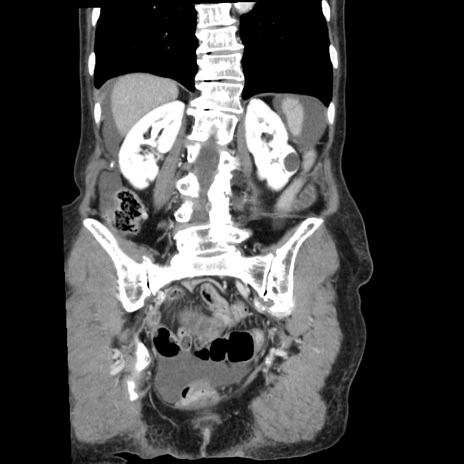

横断像

【症例】80歳代女性

【主訴】腹痛

【現病歴】8時間前から腹痛あり来院。

【既往歴】糖尿病、脂質異常症、子宮体癌にて子宮全摘術

【身体所見】意識清明・会話良好だが腹痛で苦悶様、全腹部にわたって反跳痛と圧痛あり

【データ】WBC 13600、CRP 0.14、LDH 224、CK 90